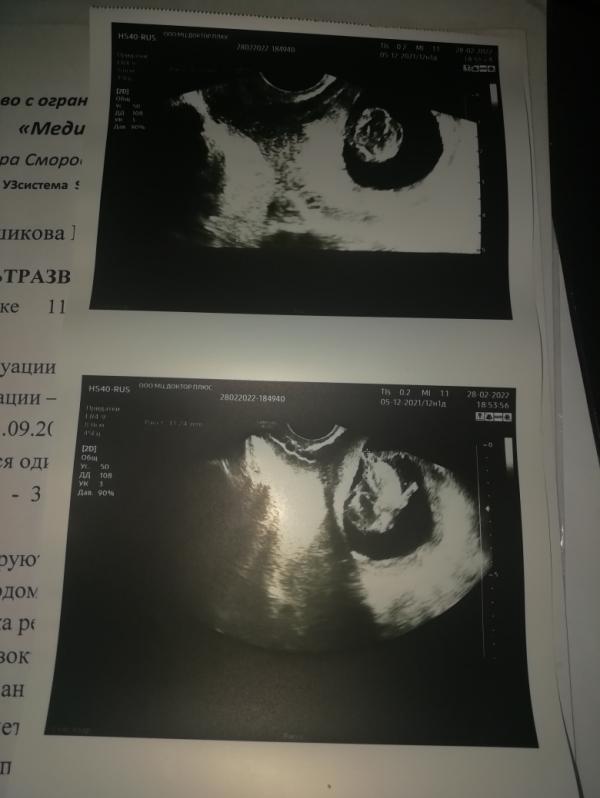

В 12 недель дали направление на первый скрининг, 28 февраля 2022г.

День Х, лежу, врач смотрит, говорит какие-то параметры, и тут слова: "у ребёнка что-то с головой..."

Далее дооолго смотрит и выбегает из кабинета, как потом оказалось к заведующей поликлиники.

Приходит, объясняет мне что такое иниоэнцефалия и что с такими детьми происходит.

Иду к заведующей, та сама сделала УЗИ и всё подтвердила.